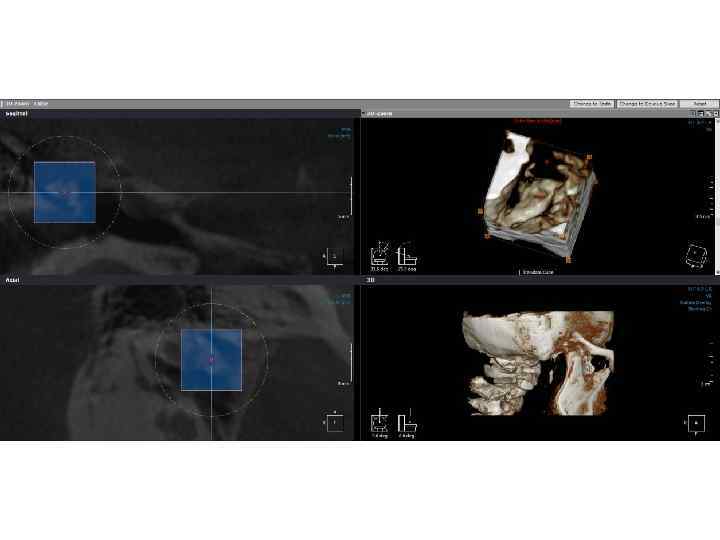

Метод объемной визуализации Point. Nix Real. Scan 2. 0 (КЛКТ) Метод объемной визуализации Point. Nix Real. Scan 2. 0 (КЛКТ)